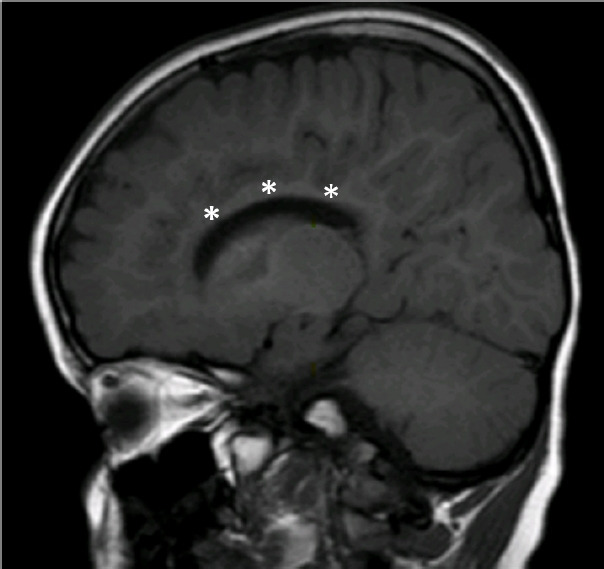

Spondyloenchondrodysplasia with immune dysregulation: an under-the-radar cause of spasticity.